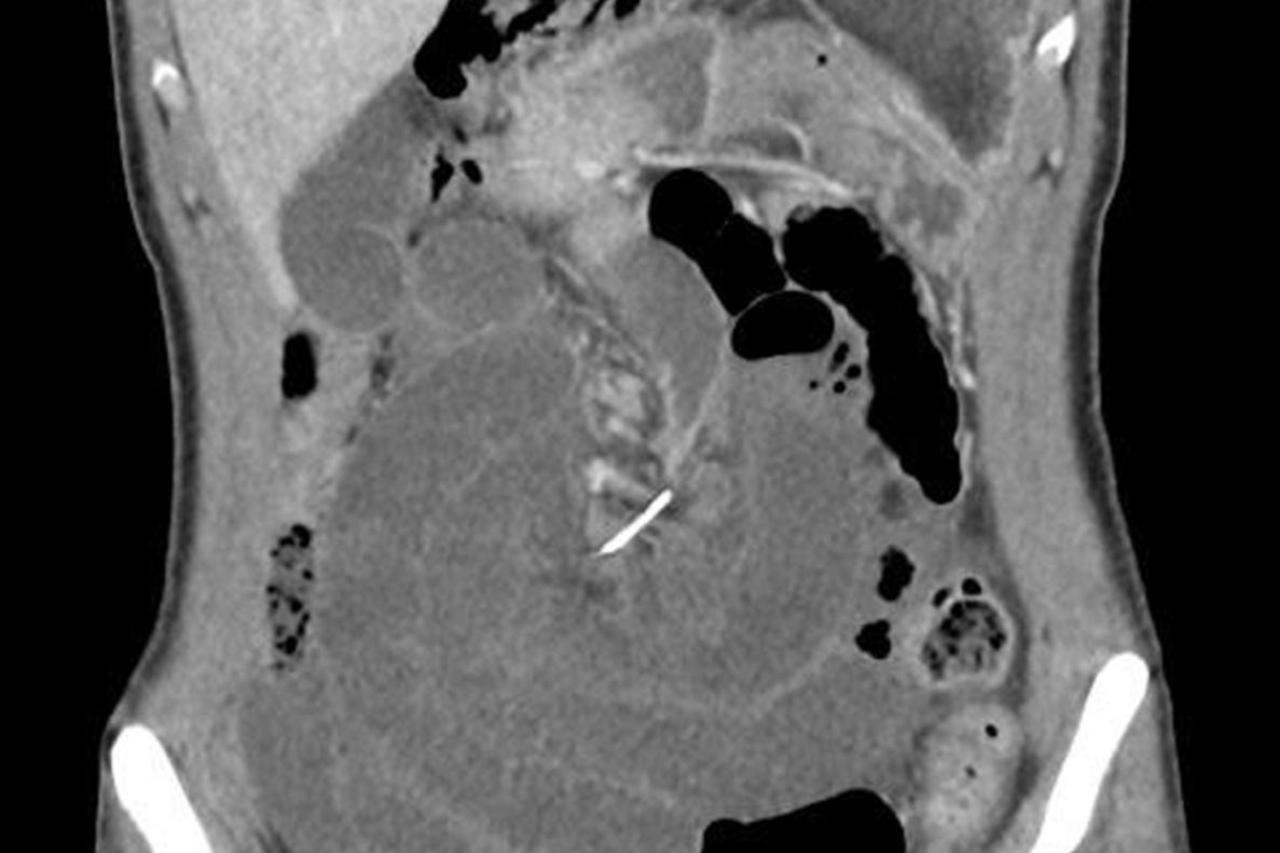

Pregled abdomena CT-om pokazao je nešto što dotad liječnici nisu vidjeli

Pregled abdomena CT-om pokazao je nešto što dotad liječnici nisu vidjeli. Kamenac težine 770 grama, dimenzija 12 x 9,5 x 7,5 centimetara, veličine je nojeva jajeta. Prosječni kamenci koje pronađu u tijelima pacijenata teže oko 1,3 grama te ih je slučaj ovog muškarca itekako začudio.

Liječnici su za The New England Journal of Medicine otkrili kako se radi o muškarcu koji je desetak godina ranije imao invazivni rak mokraćnog mjehura. U to vrijeme morali su mu ukloniti mjehur i od dijela njegovih crijeva formirati novi, što za posljedicu ima povećani rizik od nastanka kamenca, piše Live science.

Muškarac je podvrgnut operaciji kako bi kirurzi izvadili veliki kamenac, dok su druge, manje, uklonili nakon laserskog razbijanja na manje dijelove.